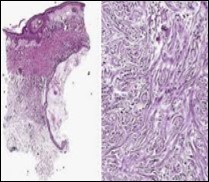

Lesions are generally superficial and infrequently invade lower dermis. Tendency for peri-neural or intra-neural infiltration, cogitated in adjunctive cutaneous carcinomas, is exceptional in desmoplastic trichoepithelioma. Nevertheless, desmoplastic trichoepithelioma can be exemplified as a component of particularly desmoplastic, cutaneous carcinomas demonstrating foci of peri-neural involvement 4, 5. Figure 1, Figure 2, Figure 3, Figure 4, Figure 5, Figure 6, Figure 7, Figure 8.

Figure 7.Desmoplastic trichoepithelioma exemplifying several keratinous horn cysts, nests of basaloid cells, a desmoplastic fibrotic stroma along with a thinned out squamous epithelial lining 14.

Figure 8.Desmoplastic fibrotic stroma demonstrating a thinned out, superimposed epithelium, fibrotic stroma and a dispersal of basaloid cell cords and aggregates 15.